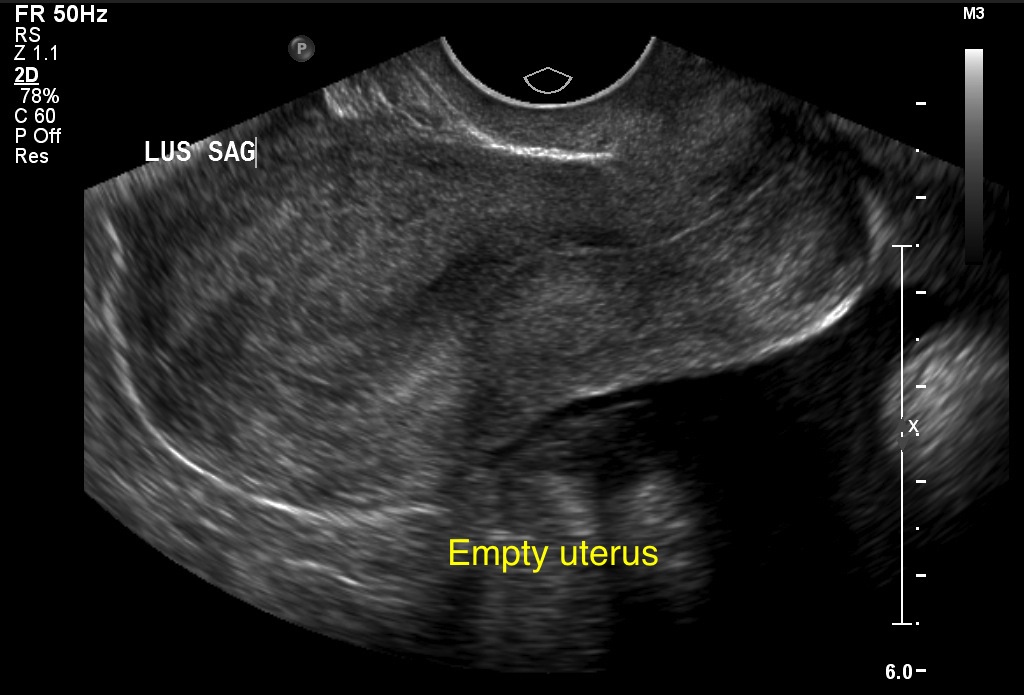

Ultrasound - The Brookside Associates

Incomplete Abortion Ultrasound is sometimes used after passage of pregnancy tissue to determine whether any pregnancy tissue remains inside the uterus. adjusting various settings for the equipment can have a significant effect on improving the images and clarifying detail. ... Fetch This Document

A : ChApter 14 - Weber State University

Abortion Definition ultrasound appearance Incomplete Spontaneous abortion in which some products of conception remain in the uterus Thickened endometrium, myometrium spontaneous abortion. 2. The two images display bony structural anomalies. ... Access Content